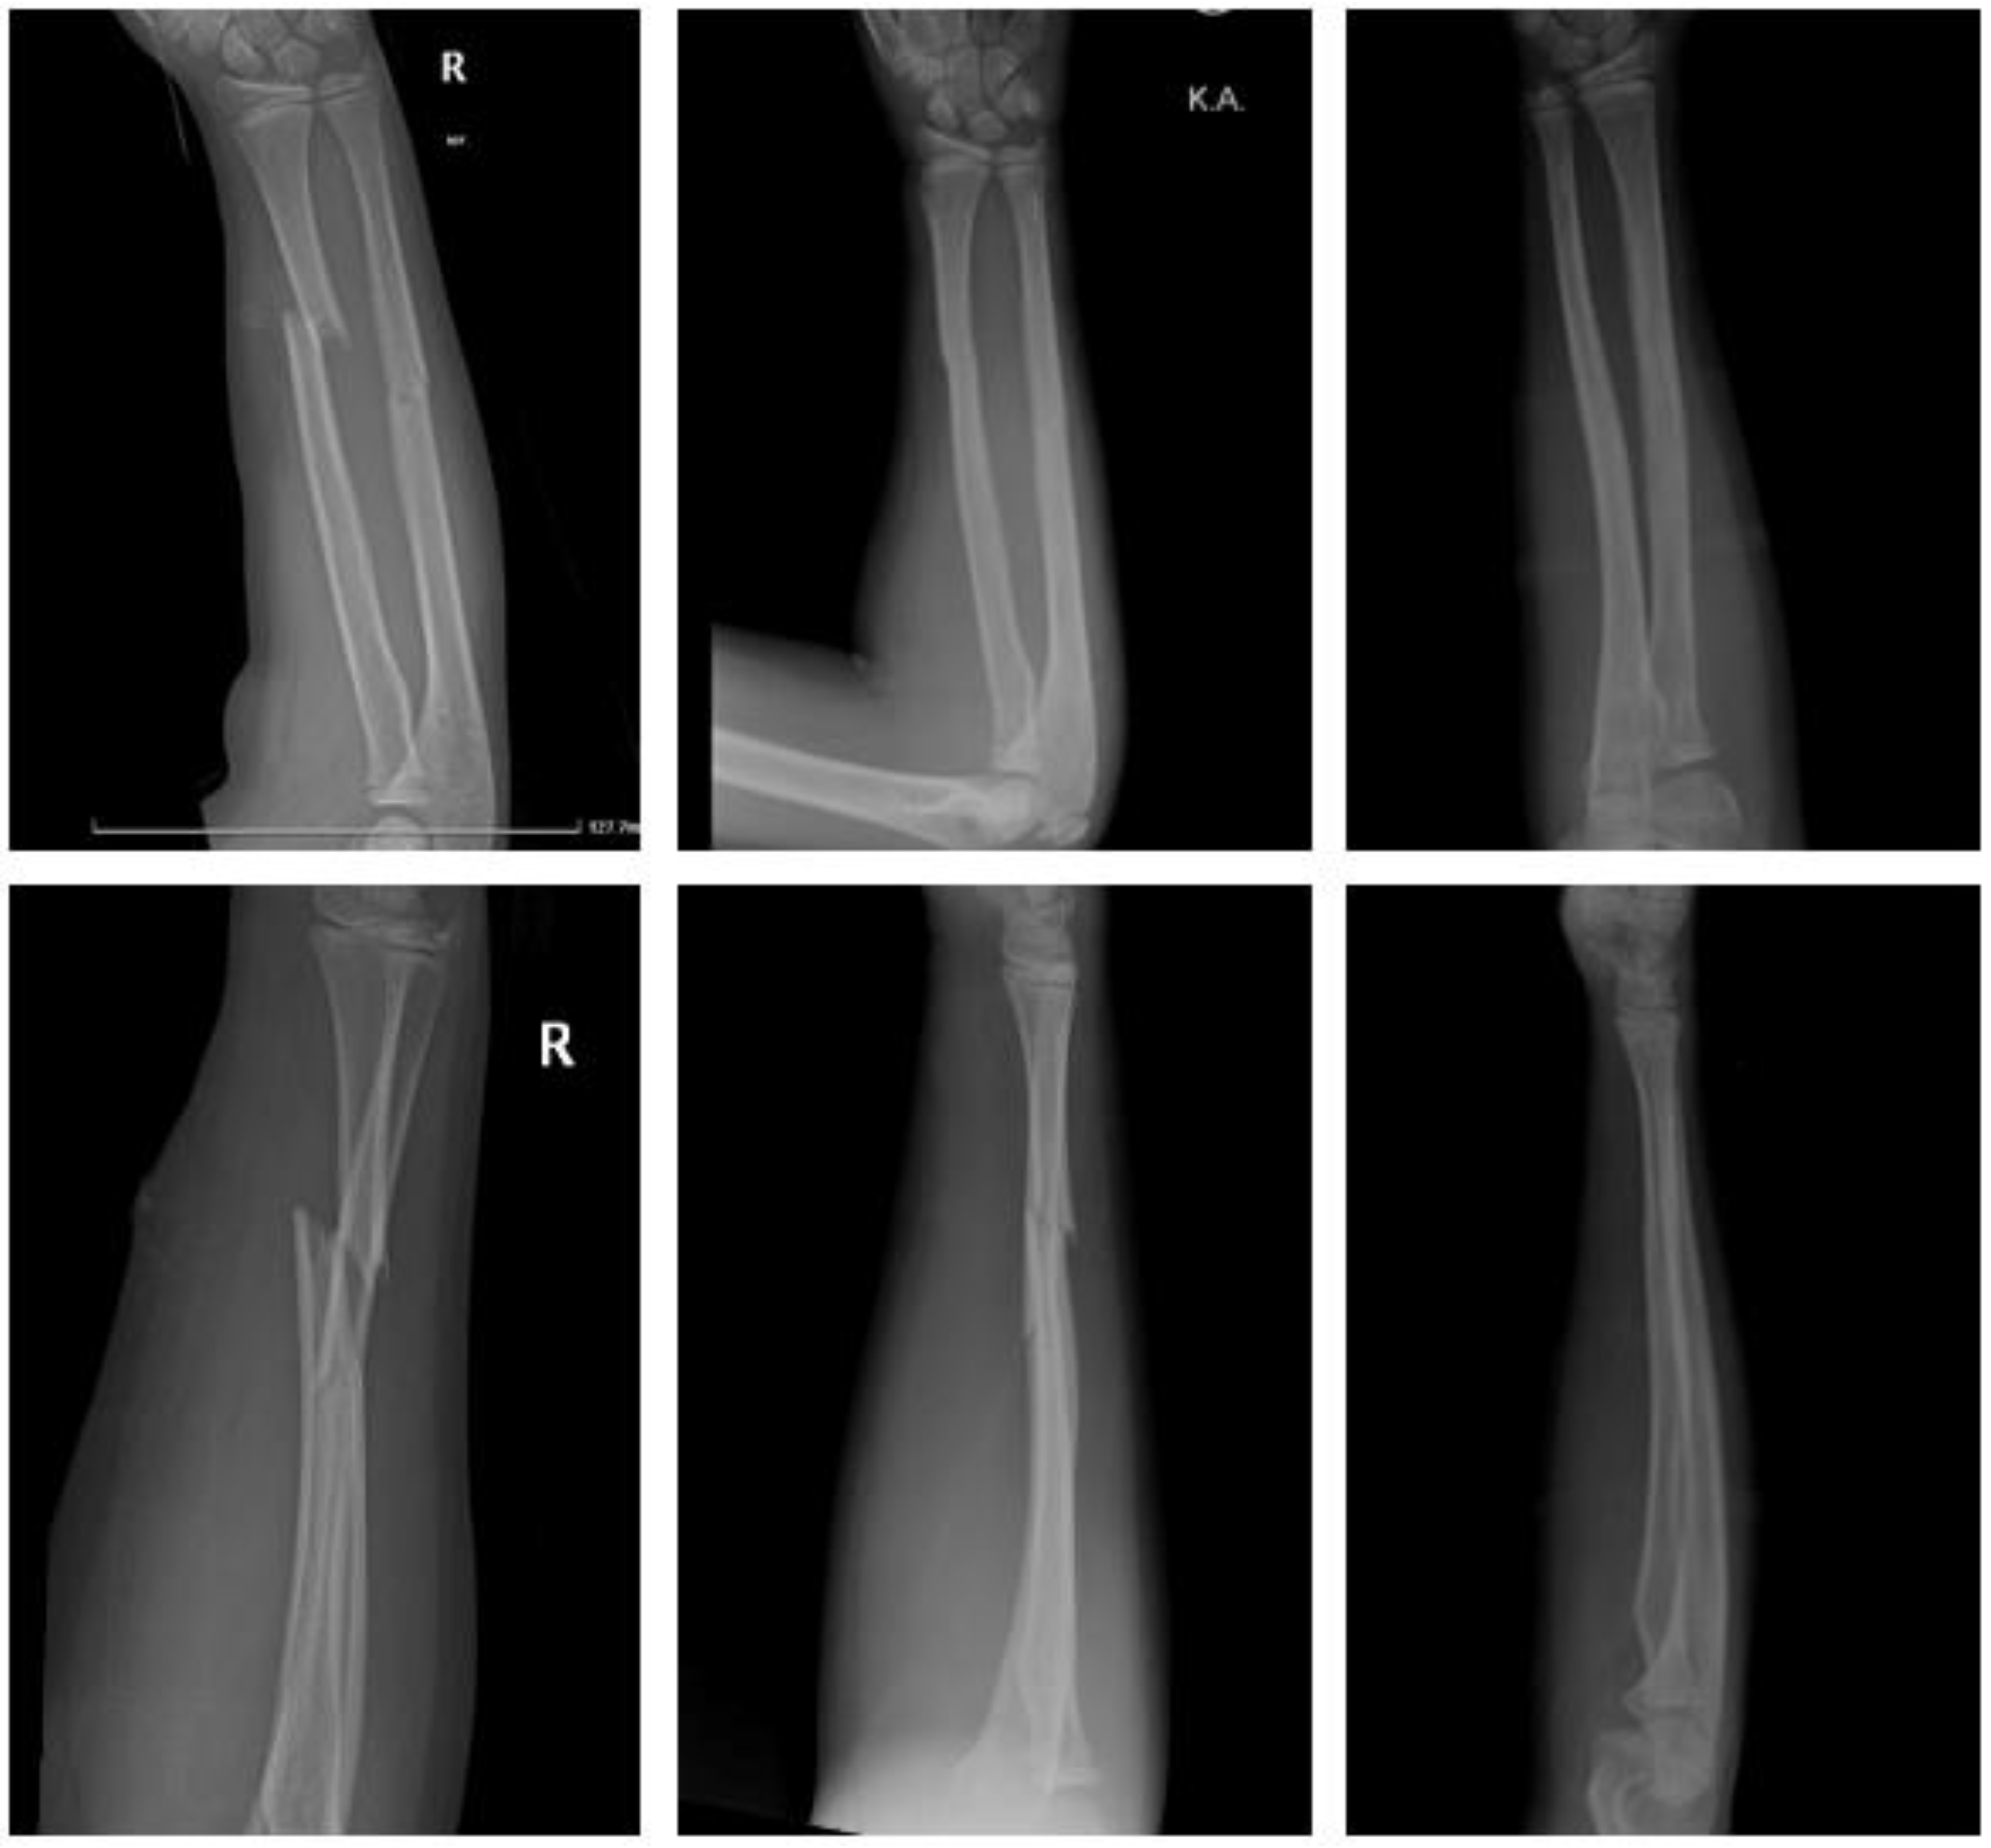

2.4.5. Fracture of the Forearm Shaft